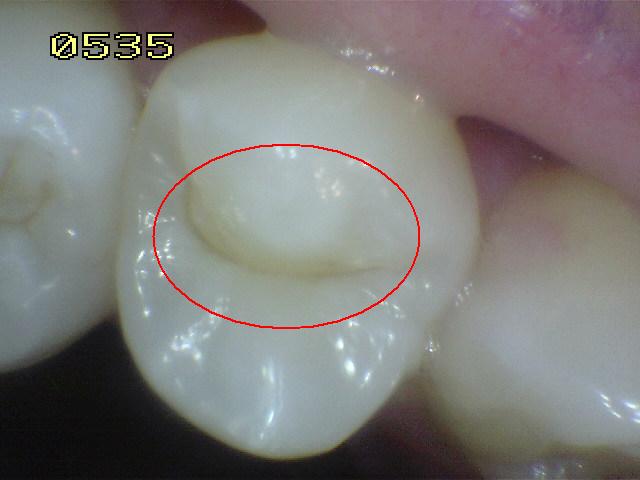

Código 2:

Lesión de caries observada en esmalte en estado húmedo y

permanece después de secar

- Al observar el

diente en estado húmedo verá una decoloración (mancha blanca

/ marrón)

en el fondo de la fosa y fisura y que desborda hacia las

paredes. (mas ancha que la fosa y fisura) las manchas

no tienen brillo y es consistente con desmineralización.